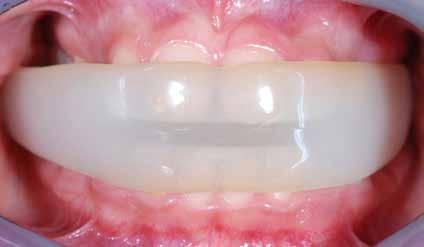

Fig. 118 > Apparecchio elastodontico all’interno del cavo orale: è possibile

apprezzare il grande lavoro che lo stesso svolge sulle strutture scheletriche, sui muscoli delle labbra e della lingua; di qui l’effetto tridimensionale della terapia elastodontica.